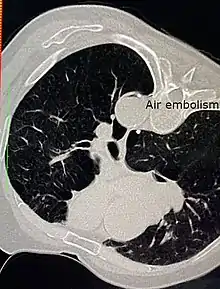

| Air embolism | |